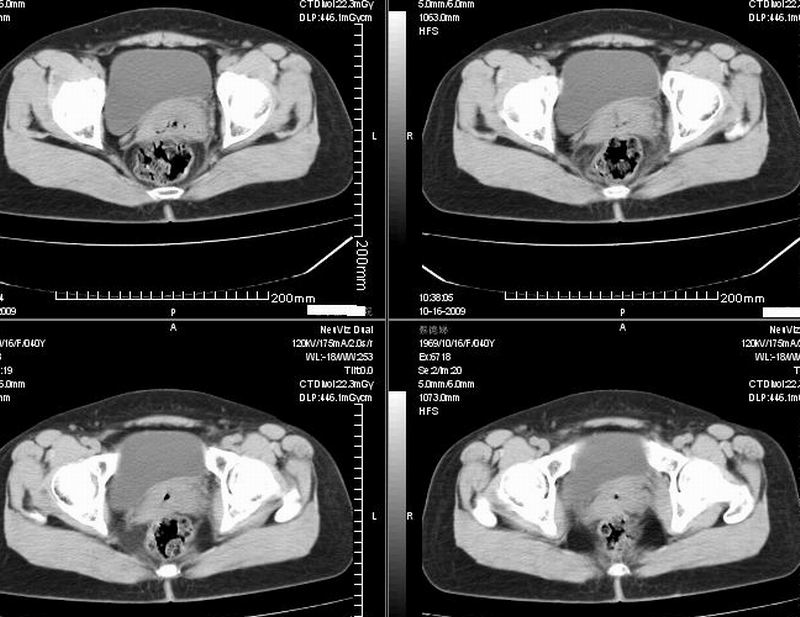

女:40y:下腹隐痛1周+,无其它不适,这个子宫会太一点吗?有临床意义吗?

宫腔内有积液,考虑炎症可能

子宫偏左,略显增大,期内可见低密度改变,考虑宫腔积液可能。

子宫偏左,略显增大,期内可见低密度改变,考虑宫腔积液可能。 不能除外肌瘤可能。

子宫体积稍增大,其内见低密度影。考虑宫腔积液可能。

子宫不规则的增大 宫腔内积液 有多种考虑

1 子宫肌瘤

2 子宫腺肌症

3 子宫内膜炎

4 月经期 (宫腔内积血)